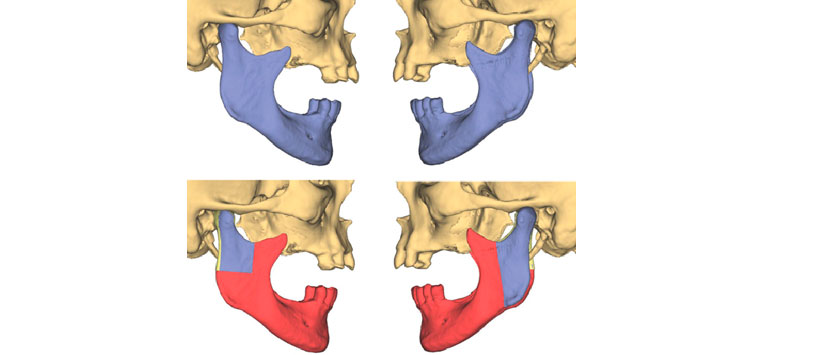

Primero, se establecieron los planos de resección de la mandíbula (Fig. 2). El tamaño del segmento mandibular que debe resecarse generalmente está determinado por la extensión de la patología a tratar. Los hallazgos clínicos y especialmente las tomografías computarizadas de diagnóstico (TC) juegan un papel clave en este contexto.

La resección mandibular virtual fue seguida por la reconstrucción virtual del defecto mandibular resultante con un colgajo de peroné que consta de seis segmentos. Este procedimiento semiautomático consistió en dividir el defecto del hueso mandibular en seis unidades con el fin de posicionar los segmentos de peroné de tal manera que pudieran llenar el defecto de manera apropiada. Después de determinar los extremos distales y proximales del sitio de osteotomía fibular, el colgajo de peroné se colocó virtualmente en el defecto utilizando un algoritmo de software (Fig. 3). Como un peroné es un hueso recto, se deben cortar cuñas del hueso para permitir que se cree la forma deseada de la mandíbula. Las líneas y los ángulos de osteotomía fueron determinados automáticamente por el software (Fig. 4). Después de un posicionamiento rugoso automático de las piezas de hueso, el ingeniero de planificación colocó manualmente los segmentos de peroné en su posición exacta al final del procedimiento de reconstrucción mandibular virtual.